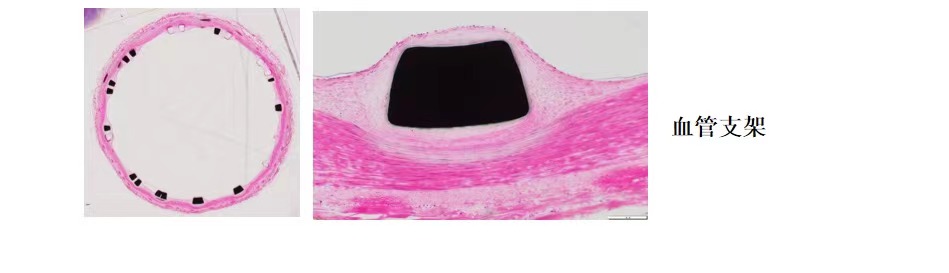

使用德国EXAKT切磨系统进行硬组织切片,特别是对于含有金属这类植入物的组织,是一种精确的组织切片技术。

各类尺寸的含金属植入物骨、牙齿、血管等硬组织样本脱水,7200树脂浸润包埋,后期用标准尺寸(25mm*75mm)的树脂片进行切磨片处理。

将包埋好的硬组织树脂块,用EXAKT 硬组织切片机先切一个200um的厚片,然后再通过EXAKT 硬组织磨片机将其磨到20-30um薄片,样本是已经硬组织包埋好的含金属的动物样本。

针对不同的病理阅片指标需求,行HE染色、Masson染色、亚甲基蓝-酸性品红染色、VG染色、Movat染色等。